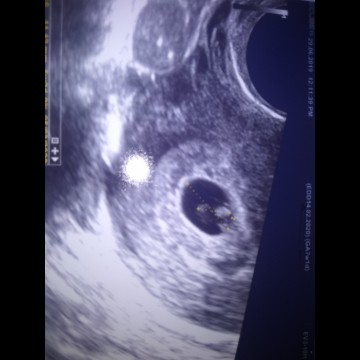

hasil USG 5week

Bunda..tadi siang saya USG transvaginal . Alhamdulillah janin nya aktif dan detak jantung nya normal dan baik . Saya USG gara gara saya flek brpa hari ini tapi Alhamdulillah cuma flek coklat dan saya di suruh bedres selama 2 Minggu . Doain ya bunda semoga baik baik saja .. amin ?